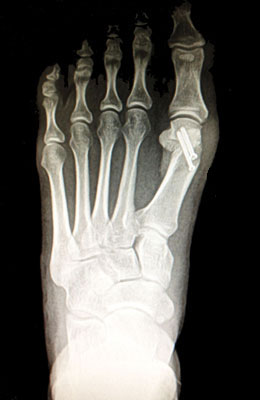

Before

Minimally Invasive Bunion Surgery featuring the CrossRoads miniBunion™ System before

After

Minimally Invasive Bunion Surgery featuring the CrossRoads miniBunion™ System after

Minimally Invasive Bunion Surgery featuring the CrossRoads miniBunion™ System

Eva is a 24-year-old female who had just began working at a job that required high fashion shoes. She was in constant pain but could not take time off work. Our miniBunion™ Minimally Invasive Bunionectomy allowed her to continue to work and be on her foot with full recovery and return to regular shoes by 6 weeks. She had an amazing range of motion, no more bunion pain, and absolutely no visible incision. After picture taken six weeks post-surgery.